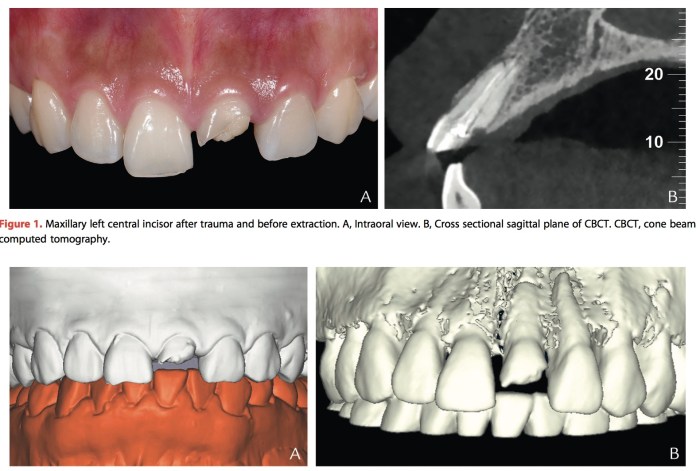

其實這篇文章的重點就是,上顎前牙的植牙臨時假牙,因為在pick up的時候不好定位,所以做兩個小翅膀是很聰明的事。那為什麼還要牽扯到數位,因為十年後可能都是這樣做的,是先學會也是件好事。